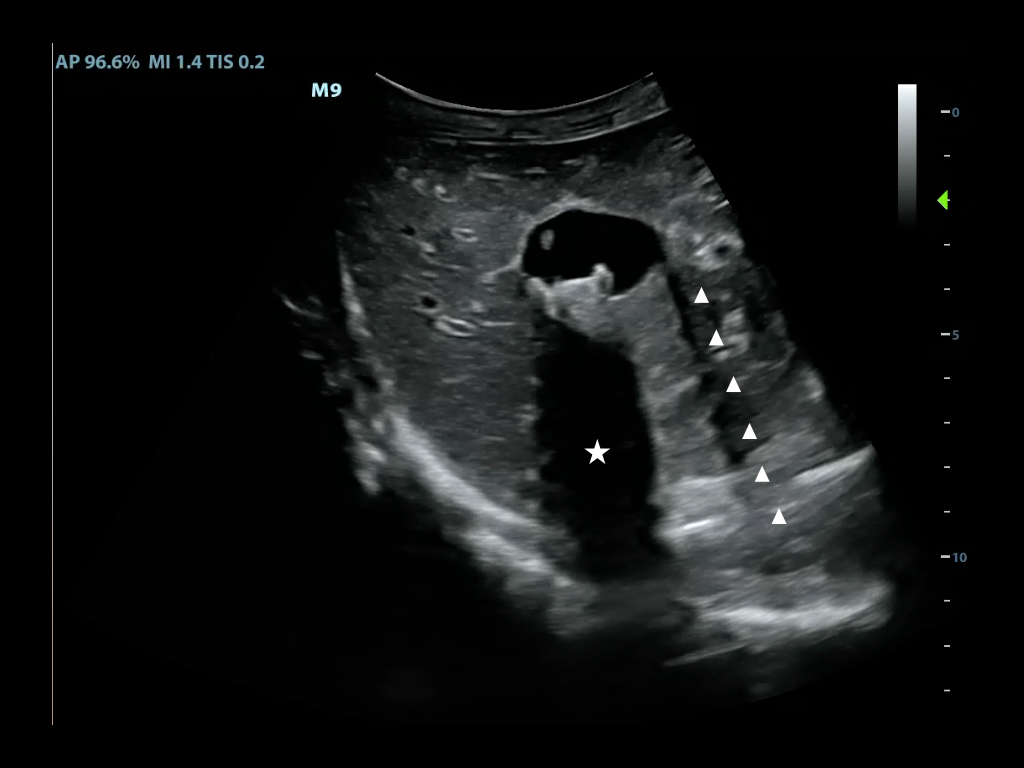

- Color Doppler ultrasound is also called color-flow ultrasound.

- It is used to show blood flow or tissue motion in a selected two-dimensional area

- Direction and velocity of tissue motion and blood flow are color coded and superimposed on the corresponding B-mode image (Figure 3, Video 2)

- Typically, red depicts movement towards the transducer, while blue depicts movement away from the transducer

- Figure 3. Color doppler showing turbulent blood flow in a large abdominal aortic aneurysm

Video 2. Color doppler showing turbulent blood flow in a large abdominal aortic aneurysm